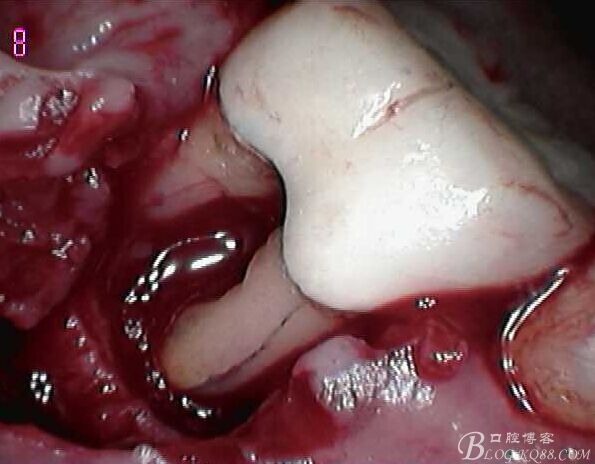

頰側(cè)翻瓣見,頰側(cè)骨壁完全缺損,同時(shí)見近遠(yuǎn)中根都有縱向裂紋,

無法保留,

建議拔除C6,延期種植,

因C5遠(yuǎn)中骨壁完全喪失,

調(diào)合觀察C5,

拔出后可見頰舌側(cè)都有縱向裂紋